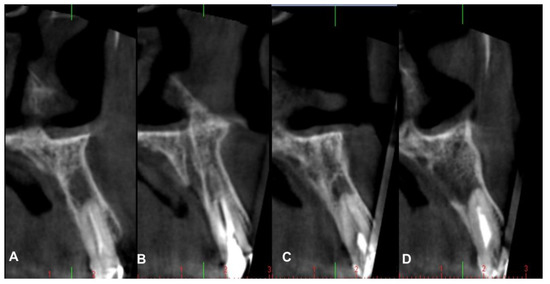

4.1. Patient No. 1

4.2. Patient No. 2

4.3. Patient No. 3

4.4. Patient No.4

4.5. Patient No.5

4.6. Patient No.6

| Patient Gender Age | Medical History of Interest [Toxic Habits] Type of Surgery | Closure by First Intention [Collagen Sponge] | I.M. | I. C. | Healing | Early Postoperative Complications | Late Postoperative Complications |

|---|---|---|---|---|---|---|---|

| 1 F 63 | NO [Tobacco: 2 cig/day] Horizontal Guided Bone Regeneration | Yes [No] | G | No | G | No | No |

| 2 M 52 | NO [-] Alveolar ridge preservation | No [Yes] | G | No | M | Graft loss and self-limited alveolitis | No |

| 3 M 61 | NO [-] Alveolar ridge preservation | Yes [No] | G | No | G | No | No osseointegration of the implant, replacement in 3 months, without problems and with good stability |

| 4 F 46 | NO [-] Alveolar ridge preservation | No [Yes] | G | No | M | Graft loss and self-limited alveolitis | No |

| 5 M 64 | NO [-] Sinus lift with lateral window | Yes [No] | G | No | G | No | No |

| 6 M 46 | NO [-] Sinus lift with lateral window | Yes [No] | G | No | G | No | No |